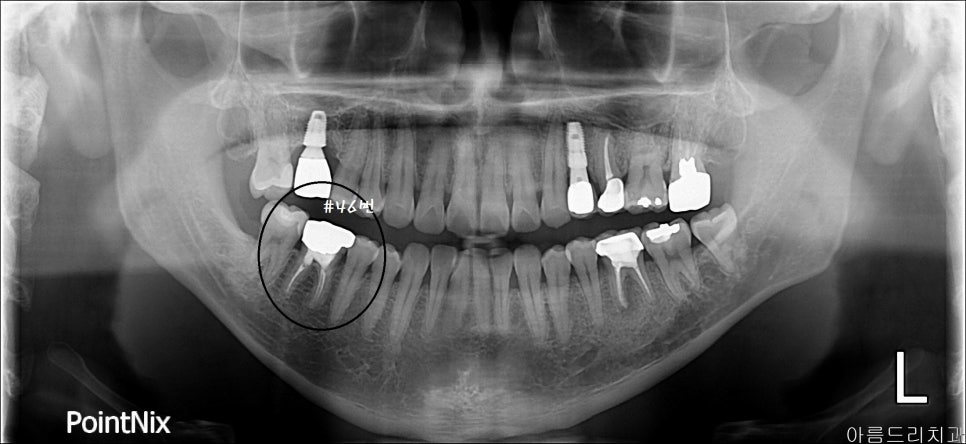

아래 환자분은 예전 신경치료받았던 부분에 문제가 생겼습니다. 지속적인 통증을 호소하셨고, 약을 복용하면서 지켜봐온 상태이며, 발치하긴 전 재식을 선택해 보기로 했습니다. 오른쪽 6번째 치아인 #46번 치아 치료 과정으로 재식을 설명드려볼까 합니다.